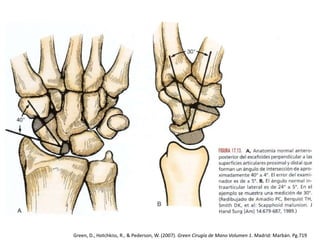

ANATOMÍA

• Recubierto de cartílago

• 5 Superficies articulares

– Radio

– Semilunar

– Hueso grande

– Trapecio

– Trapezoide

• Superficie distal palmar

respecto a la proximal

• Inserciones ligamentosas

– L. interóseo escafolunar

– L. radioescafogrande

– L. trapecioescafoideo

– L. escafogrande

Criterios de Inestabilidad

• Desplazamiento > 1mm en Rx AP u Oblicua

• Angulo Hueso grande-semilunar > 15º (Rx L)

• Angulo escafosemilunar > 45º (Rx L)

• Conminución

• Inestabilidad del carpo